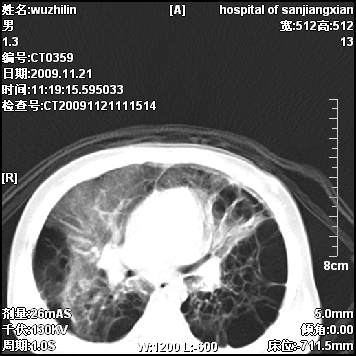

弥漫性薄壁囊腔,胸膜下及肺底部占优势,双上肺磨玻璃密度影,首先考虑特发性肺间质纤维化,其次囊性肺纤维化,肺淋巴管平滑肌瘤病嗜酸性肉芽肿等;要结合临床综合考虑。

两肺布满多个薄壁含气囊腔,以下肺居多,伴磨玻璃样密度影,左侧气胸。两肺发育不全、两肺多发肺囊肿并感染,其次考虑肺囊腺瘤。